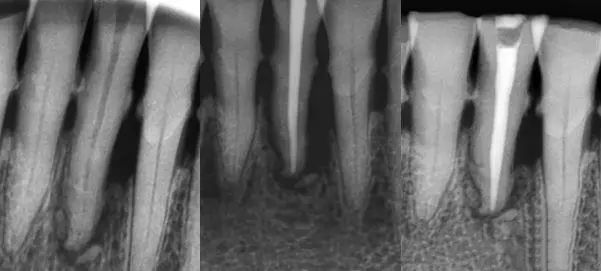

一 主尖选择原则

首选锥度等于或稍小于主锉,粗细型号等同于主锉,比如主锉首选6%25#,如果粗了选择6%20#,如果细了选择6%30#。主尖合适后在尖端3mm要有牵拉感,而且施加合适的力量主尖也不会超出狭窄部。